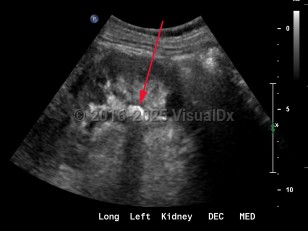

Imaging Studies image of Renal calculus - imageId=8341825. Click to open in gallery.  caption: '<span>Grayscale ultrasound of the left kidney demonstrates an echogenic focus in the lower pole with shadowing artifact.</span>'

Grayscale ultrasound of the left kidney demonstrates an echogenic focus in the lower pole with shadowing artifact.